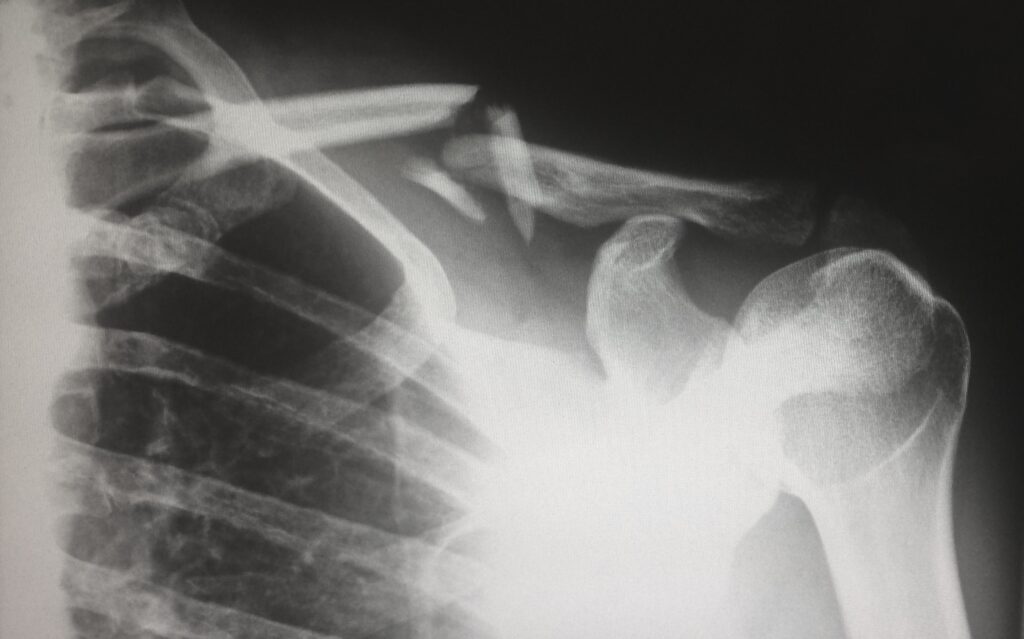

Los doctores podrían solicitar una radiografía para examinar los huesos y tejidos del brazo y hombro. Para obtener un diagnóstico más completo, también podrían recomendar una resonancia magnética o un ultrasonido, según si el desgarro del manguito rotador es parcial o completo.